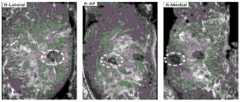

图6为被检查者A左侧乳房的C平面超声图像数据在检测深度为12.454mm,检测位置为AP(前后),Lateral(侧面)时的超声图像。Fig. 6 is the ultrasound image of the C-plane ultrasound image data of the left breast of the examinee A when the detection depth is 12.454 mm, and the detection positions are AP (front and rear) and Lateral (side).

图7为被检查者A左侧乳房的C平面超声图像数据在检测深度为12.454mm,检测位置为AP(前后),Lateral(侧面)时的超声图像经过自动定位标记乳头位置后的实验结果,其中白色虚线圆环标记位置即为乳头位置。Figure 7 shows the experimental results of the ultrasonic image data of the C-plane of the left breast of the examinee A when the detection depth is 12.454 mm, the detection position is AP (front and rear), and Lateral (side) after automatic positioning and marking the nipple position, The white dotted circle marks the position of the nipple.

图8为被检查者A左侧乳房的C平面超声图像数据在检测深度为12.454mm,检测位置为AP(前后),Lateral(侧面)时的超声图像经过本发明算法拼接之后的结果。Fig. 8 shows the result of the ultrasonic image data of the left breast of the examinee A when the detection depth is 12.454mm, the detection position is AP (front and rear), and the ultrasonic image is spliced by the algorithm of the present invention.

图12为被检查者B右侧乳房的C平面超声图像数据在检测深度为9.123mm,检测位置为AP(前后),Lateral(侧面),Medial(中间)时的超声图像。Figure 12 is the ultrasound image of the C-plane ultrasound image data of the right breast of the examinee B when the detection depth is 9.123 mm, and the detection positions are AP (front and rear), Lateral (side), and Medial (middle).

图13为被检查者B右侧乳房的C平面超声图像数据在检测深度为9.123mm,检测位置为AP(前后),Lateral(侧面),Medial(中间)时的超声图像经过自动定位标记乳头位置后的结果,其中白色虚线圆环标记位置即为乳头位置,另一明显区别于正常组织的位置为肿瘤。Figure 13 shows the ultrasound image data of the C-plane of the right breast of the examinee B when the detection depth is 9.123mm, and the detection positions are AP (front and rear), Lateral (side), and Medial (middle) The ultrasound image is marked with the nipple position after automatic positioning In the latter results, the position marked by the white dotted circle is the position of the nipple, and the other position that is significantly different from the normal tissue is the tumor.

图14为被检查者B右侧乳房的C平面超声图像数据在检测深度为9.123mm检测位置为AP(前后),Lateral(侧面),Medial(中间)时的超声图像经本发明算法拼接之后的结果。Figure 14 is the ultrasonic image data of the C plane of the right breast of the examinee B when the detection depth is 9.123mm and the detection positions are AP (front and rear), Lateral (side), and Medial (middle) after the ultrasonic images are spliced by the algorithm of the present invention result.

S1:读取实验所需的ABUS三维超声图像数据。本步骤的实验获取结果可由图6,图9和图12可见。S1: Read the ABUS 3D ultrasound image data required for the experiment. The experimental results of this step can be seen in Figure 6, Figure 9 and Figure 12.

(1)正确读取ABUS图像数据的具体步骤为:首先,新读取一例ABUS乳腺超声图像数据,然后判断读取后数据中是否含有待拼接的不同扫描位置,例如:AP(前后),Lateral(侧面),Medial(中间),如图4和图5所示,若判断为含有不同扫描位置,则进行下一步骤,此过程中使用到RadiAnt DICOM Viewer软件。在正确读取后的ABUS图像数据中包含了H平面(横断面),S平面(矢状面),C平面(冠状面)三个平面的图像数据,如图3所示,在这三个平面中自动选择C平面超声图像数据进行后续处理。实验中选取一被检查者A的一例ABUS乳腺图像数据进行实验,此例数据包含了左右两边乳房的AP(前后),Lateral(侧面)位置。为证明实验的可靠性,再次选取被检查者B的一例超声图像数据进行与被检查者A相同的后续处理,此例数据包含右边乳房的AP(前后),Lateral(侧面),Medial(中间)这三个检测位置。(1) The specific steps for correctly reading ABUS image data are: first, read a new case of ABUS breast ultrasound image data, and then determine whether the read data contains different scanning positions to be spliced, such as: AP (front and rear), Lateral (side), Medial (middle), as shown in Figure 4 and Figure 5, if it is determined that it contains different scanning positions, then proceed to the next step, and the RadiAnt DICOM Viewer software is used in this process. The correctly read ABUS image data includes the image data of the H plane (transverse section), the S plane (sagittal plane), and the C plane (coronal plane). As shown in Figure 3, in these three planes C-plane ultrasound image data is automatically selected in the plane for subsequent processing. In the experiment, a case of ABUS breast image data of a subject A was selected for the experiment. The data of this case included the AP (front and rear) and Lateral (lateral) positions of the left and right breasts. In order to prove the reliability of the experiment, another case of ultrasound image data of examinee B was selected for the same follow-up processing as that of examinee A. The data of this example included AP (front and rear), Lateral (side), and Medial (middle) of the right breast. the three detection positions.

(2)根据这些不同扫描位置的实验数据,利用3D Slicer软件选择其中处于同一扫描深度的C平面图像数据作为实验图像数据。实验中选取被检查者A处于深度为12.454mm的图像数据进行实验,选取后的图像如图6和图9所示,通过实验分别拼接左右两侧,可以观察到此被检查者的右边乳房患有癌症,左边乳房正常,拼接结果形成对比,可以清楚观察到患有癌症的乳腺组织和正常乳腺组织的结构外貌差别,使医生的诊断结果也更具准确性和客观性。实验中选取被检查者B处于深度为9.123mm的图像数据进行实验,选取后的图像如图12所示。通过拼接此例超声图像,医生可以清楚地观察到被检查者的整个右边乳腺组织,可以完整地观察到肿瘤所在位置,大致形状和大小,此实验即可直观反映超声全景图在准确和客观地诊断乳腺癌筛查病例中的优势以及在临床的实际应用价值。(2) According to the experimental data of these different scanning positions, use the 3D Slicer software to select the C-plane image data at the same scanning depth as the experimental image data. In the experiment, the image data of the examinee A at a depth of 12.454mm was selected for the experiment. The selected images are shown in Figure 6 and Figure 9. Through the experiment, the left and right sides were spliced respectively, and it can be observed that the examinee's right breast is affected. There is cancer, the left breast is normal, and the splicing results are contrasted, and the difference in the structure and appearance of the cancerous breast tissue and the normal breast tissue can be clearly observed, which makes the doctor's diagnosis more accurate and objective. In the experiment, the image data of the examinee B at a depth of 9.123 mm was selected for the experiment, and the selected image is shown in Figure 12. By splicing the ultrasound images of this case, the doctor can clearly observe the entire right breast tissue of the examinee, and can completely observe the location, approximate shape and size of the tumor. This experiment can intuitively reflect that the ultrasound panorama is accurate and objective. Advantages in diagnosing breast cancer screening cases and practical application in clinic.

S2:自动定位乳头位置过程。本步骤的实验识别和标记结果可由图7,图10和图13可见。S2: Automatically locate the nipple position process. The experimental identification and labeling results of this step can be seen in Figure 7, Figure 10 and Figure 13.

(1)提取实验图像数据的ROI区域并分别对提取后的ROI做出相应的预处理,然后完成图像二值化,开闭和反相运算的过程,最后删除与实验图像边框相连的白色区域和小面积白色目标,即完成进行乳头位置检测实验前的图像数据准备过程。(1) Extract the ROI area of the experimental image data and perform corresponding preprocessing on the extracted ROI, then complete the process of image binarization, opening and closing and inversion operations, and finally delete the white area connected to the border of the experimental image. and a small area white target, that is, the image data preparation process before the nipple position detection experiment is completed.

(2)利用Hough变换圆检测完成自动定位标记乳头位置过程;实验采用Hough变换圆检测算法,对于ABUS乳腺超声图像中的任意一个边缘点I(x,y),分别以Δθ和Δr的步长遍历图像,得到参数空间(a,b,r)的子空间,并对相应的累加器单元A(a,b,r)加1。对二值图像的所有像素点遍历之后,得到累加器数组A,其中任意一个数组元素表示半径为r,圆心为(a,b)的圆上边缘点数目,得出A(a,b,r)的最大值,当其值大于80,即找到了圆形位置。根据提高Hough变换识别圆形物体准确率的方法排除误判圆。识别完成之后,还需排除错误识别,判断累加单元A与标准差σ的比值K是否大于1,大于1属于正确识别,小于1则属于错误识别,在实验中除去大于1的情况,最终正确确定乳头的所在位置坐标。通过实验拼接超声图像,被检查者A的左侧乳房通过自动定位标记乳头位置的结果为图7,右侧乳房通过自动定位标记乳头位置的结果为图10,被检查者B的右侧乳房通过自动定位标记乳头位置的结果为图13,其中利用白色虚线圆环标记的位置即为乳头位置。(2) The Hough transform circle detection is used to complete the process of automatically positioning and marking the nipple position; the experiment adopts the Hough transform circle detection algorithm. For any edge point I(x, y) in the ABUS breast ultrasound image, the steps of Δθ and Δr are used respectively. Traverse the image to obtain a subspace of the parameter space (a, b, r) and add 1 to the corresponding accumulator unit A(a, b, r). After traversing all the pixel points of the binary image, the accumulator array A is obtained, and any array element represents the number of edge points on the circle with the radius r and the center of the circle (a, b), and obtains A(a, b, r ), when its value is greater than 80, the circular position is found. Eliminate misjudged circles according to the method of improving the accuracy of Hough transform to identify circular objects. After the identification is completed, it is necessary to eliminate the wrong identification, and judge whether the ratio K of the accumulation unit A and the standard deviation σ is greater than 1. If it is greater than 1, it is a correct identification, and if it is less than 1, it is a wrong identification. The coordinates of the location of the nipple. Through the experiment splicing ultrasound images, the result of marking the position of the nipple on the left breast of examinee A through automatic positioning is shown in Figure 7, and the result of marking the position of the nipple on the right breast through automatic positioning is shown in Figure 10, the right breast of the examinee B passes through The result of automatic positioning marking the position of the nipple is shown in Figure 13, where the position marked with the white dotted circle is the position of the nipple.